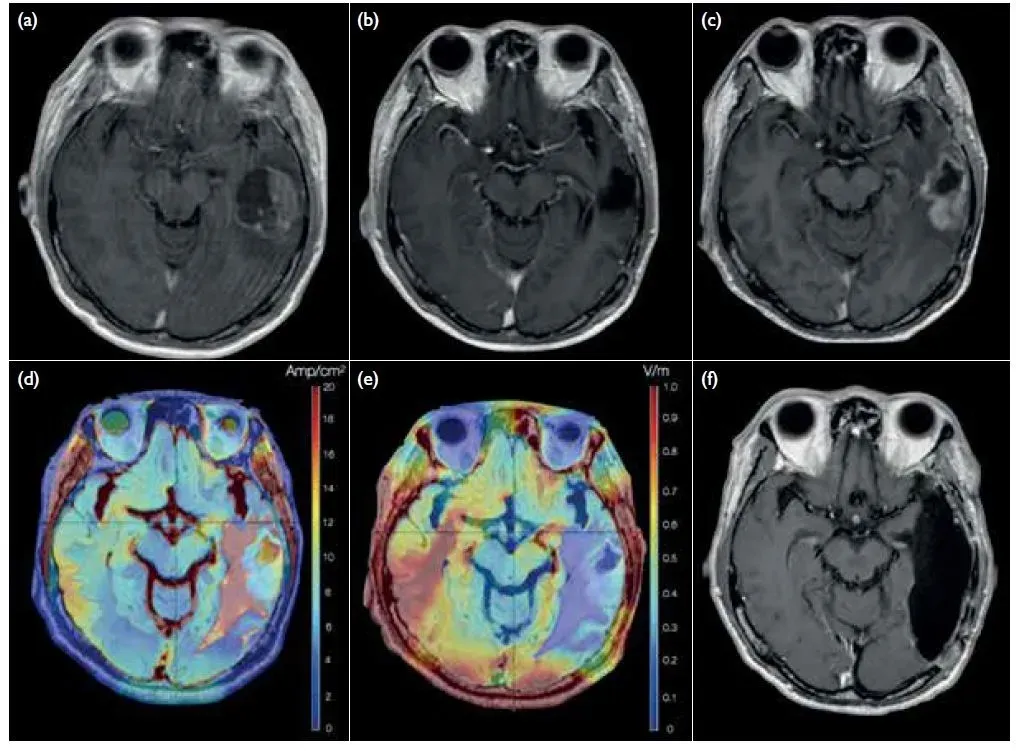

《香港医学杂志》曾报道过一则典型案例:一名55岁男性胶质母细胞瘤患者,术后接受电场治疗(TTF)后存活超3年。该患者2018年5月因头痛、呕吐及全身性癫痫入院,磁共振成像显示左侧颞中回存在不均匀增强的脑内肿瘤,且伴有肿瘤内出血(图1a)。随后接受开颅全肿瘤切除术(图1b),组织病理学诊断为IDH-1野生型、MGMT启动子未甲基化的胶质母细胞瘤。术后,患者接受替莫唑胺(TMZ)同步放化疗联合电场治疗(TTF),共完成6个周期替莫唑胺治疗后拒绝进一步化疗,仅依靠TTF控制肿瘤达12个月。治疗前,其欧洲癌症研究与治疗组织整体生活质量(EORTCQLQ-C30)评分为67/100;治疗6个月后,该评分提升至84/100。

诊断后18个月,患者出现局部肿瘤复发,遂接受第二次开颅手术及全切除术(图1c),术后采用二线洛莫司汀化疗联合TTF治疗。治疗后,患者ECOG状态为1,生活质量良好,截至2022年已存活45个月(超3年),远高于传统治疗预估的15个月中位总生存期。

▼该患者治疗前后影像学对比图

▲图源“Hong Kong Med J”,版权归原作者所有,如无意中侵犯了知识产权,请联系我们删除